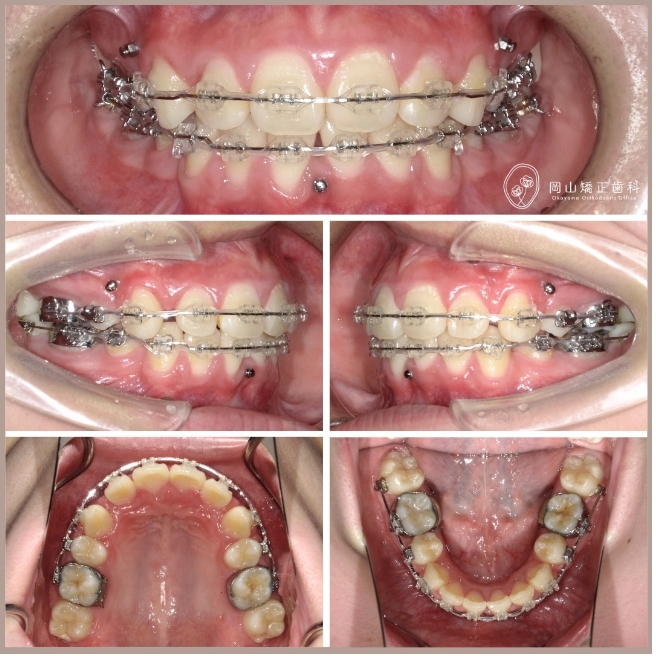

症例01

症例詳細

| 診断名 | 叢生と過蓋咬合を伴う上顎前突症例 |

| 治療装置 | マルチブラケット矯正装置(ワイヤー矯正) |

| 抜歯部位 | 上顎両側第1小臼歯、下顎両側第1小臼歯 |

| 治療期間 | 2年11ヶ月 |

治療の過程